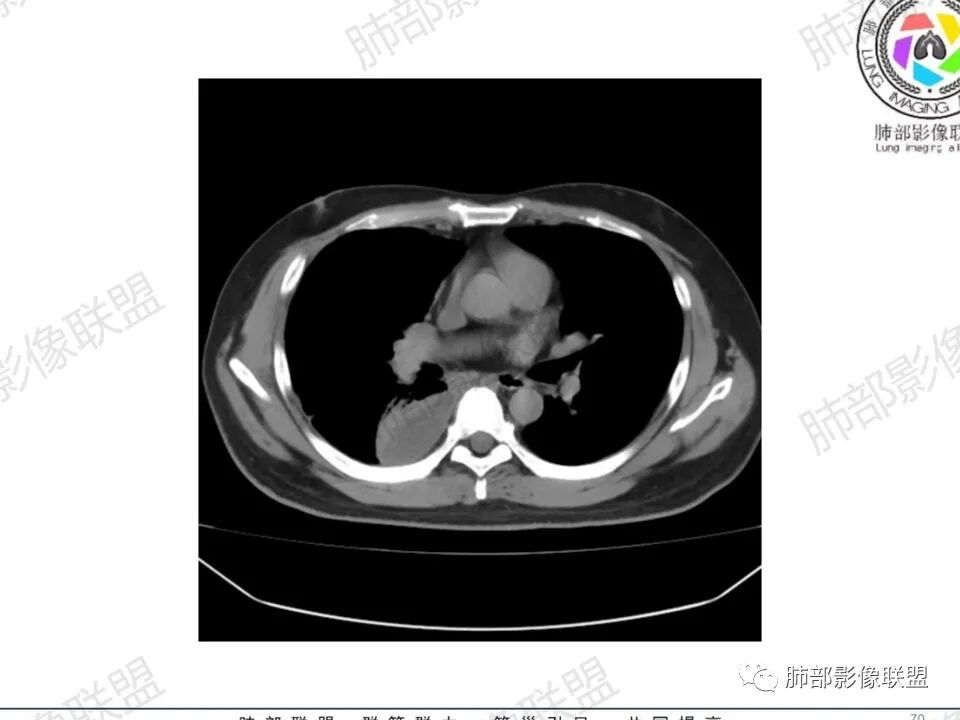

空洞内壁光滑,偏心厚壁空洞,张力高

胸水,部分包裹

支持血道来源感染性病变,金葡菌肺炎首选